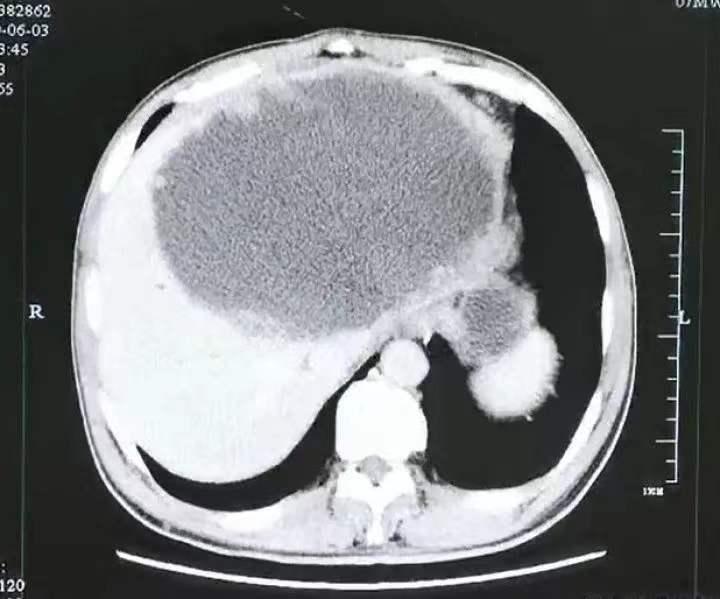

谁知当晚,老刘便出现咳嗽、高烧等症状,就医检查后老刘看着检查结果只觉得头皮发麻:

他的右边小半个肝脏都已经被“掏空了”,此时已经是一个巨大的网球状空洞形脓球,和一个三斤重的西瓜差不多大。

经进一步检查,老刘被确诊为华支睾吸虫感染。虽然手术前老刘已经有了心理准备,但看到肝脓肿内部时,还是起了一身鸡皮疙瘩。只见里面已经爬满了灯泡状的华支睾吸虫虫卵,数量多得数不清...